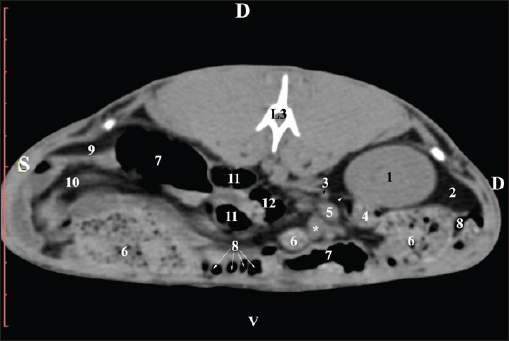

At the L2 level, the right kidney was in contact with the liver’s proc. caudatus, pars descendens of the duodenum, and the ileum. Pelvis renalis was a distinct hypoattenuated funnel-shaped soft tissue finding, whose narrow end pointed at the renal hilum and passed into the ureter. Recessus renalis was a clearly visible hypoattenuated widening of the central part of the renal pelvis in the dorsal and ventral directions (Figs. 4 and 5).

Fig. 4. Pre-contrast CT anatomical scan of the regio-abdominis media at the cranial L2 edge level. (1) Ren dexter; (2) pelvis renalis; (3) lobus caudatus (proc. caudatus) with visceral adipose tissue; (4) pars descendens of the duodenum; (5) ileum; (6) jejunum; (7) colon ascendens; (8) cecum; (9) colon transversum; (10) colon descendens; (11) lien; (12) pars transversa of the duodenum ; (*) ureter; (white arrow) recessus renalis.

Fig. 5. Pre-contrast computed tomography (CT) anatomical scan of the regio-abdominis media at the caudal L2 edge level. (1) Ren dexter; (2) pelvis renalis; (3) lobus caudatus (proc. caudatus) with visceral adipose tissue; (4) gl. adrenalis dextra; (5) ileum; (6) jejunum; (7) colon ascendens; (8) cecum; (9) colon transversum; (10) colon descendens; (11) lien; (*) ureter; (white arrow) recessus renalis.

The transverse pre-contrast examination of the regio abdominis media at the L3 level (through the cranial part of the vertebra) revealed the left kidney’s extremitas cranialis as an oval soft tissue with normoattenuated soft tissue characteristics. Ventrally, the kidney was adjacent to the duodenal pars ascendens, ileum, colon ascendens, and colon descendens. Hypoattenuated abdominal adipose collections were observed around it (Figs. 8 and 9).

Fig. 8. Pre-contrast computed tomography (CT) anatomical scan of the regio-abdominis media at the cranial L3 edge level. (1) Ren sinister; (2) adipose collections; (3) cecum; (4) colon ascendens; (5) jejunum; (6) pars ascendens of the duodenum; (7) colon descendens; (8) colon transversum; (9) colon descendens.

Fig. 9. Pre-contrast computed tomography (CT) anatomical scan of the regio-abdominis media at the caudal L3 edge level. (1) Ren dexter; (2) adipose collections; (3) cecum; (4) colon ascendens; (5) jejunum; (6) pars ascendens of the duodenum; (7) colon descendens.

At the L2 level, the renal pelvis was clearly visible as a funnel-shaped hyperattenuated soft tissue with well-demarcated hypoattenuated recesses. The transition of the renal pelvis into the relatively hypoattenuated ureter was without a distinct boundary. The post-contrast CT scan did not reveal the renal cortex and medulla margins or the presence of adipose and fibrous capsules (Fig. 16).

Fig. 16. Post-contrast computed tomography (CT) anatomical scan of the regio abdominis cranialis at the L2 level: (1) ren dexter; (2) processus caudatus; (3) pelvis renalis; (4) ureter; (5) aorta abdominalis; (6) a. renalis; (7) gl. adrenalis dextra; (8) pars descendens of the duodenum; (9) ileum; (10) cecum; (11) jejunum; (12) colon ascendens; (13) colon descendens; (14) lien; (black arrowheads) recessus renalis.

The L3 scan revealed the caudal end of the kidney as a hyperattenuated oval finding. The right ureter was medially located to it. The capsula adiposa was relatively hypoattenuated and covered the fine contours of the capsula fibrosa. The beginning of the left kidney’s extremitas cranialis appeared as an oval hypoattenuated soft tissue (Fig. 17).

Fig. 17. Post-contrast computed tomography (CT) anatomical scan of the regio-abdominis cranialis at the L3 level: (1) Ren dexter; (2) ureter ; (3) aorta abdominalis; (4) V. cava caudalis; (5) adipose collections; (6) cecum; (7) colon ascendens; (8) Ren sinister; (9) colon transversum; and (10) colon descendens.